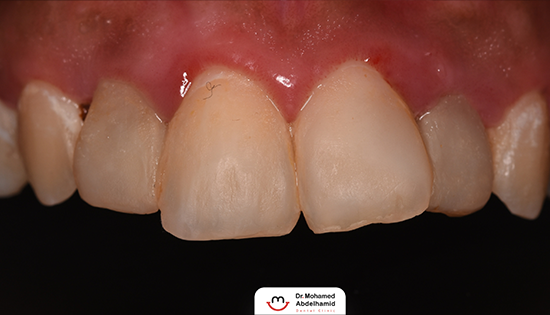

يلجأ الشخص إلى تحسين شكل أسنانه عن طريق فينير الأسنان أو ما يطلق عليه (عدسات الأسنان اللاصقة) وهي عبارة قشرة رقيقه يتم لصقها على السطح الخارجي للأسنان مصنوعة من مواد صلبة ذات معامل شفافيه مطابق للأسنان الطبيعيه   لعلاج مشكلة الاصفرار أو عدم التساوي والعديد من المشاكل الأخرى، حتى يحصل الشخص على ابتسامة رائعة تشبه ابتسامة نجوم هوليود.

• نقوم بتحضير الأسنان باستخدام الميكروسكوب لضمان اعلى قدر من الدقه في كل مراحل تنفيذ الڤينيرز.

• نقوم بأخذ مقاسات الأسنان digitally باستخدام ال intra oral scanner والذي يعد ثوره في طب الاسنان الرقمي بدون الحاجات إليى استخدام المقاسات التقليديه لضمان نسبة خطأ تكاد تكون منعدمه تقريباً.